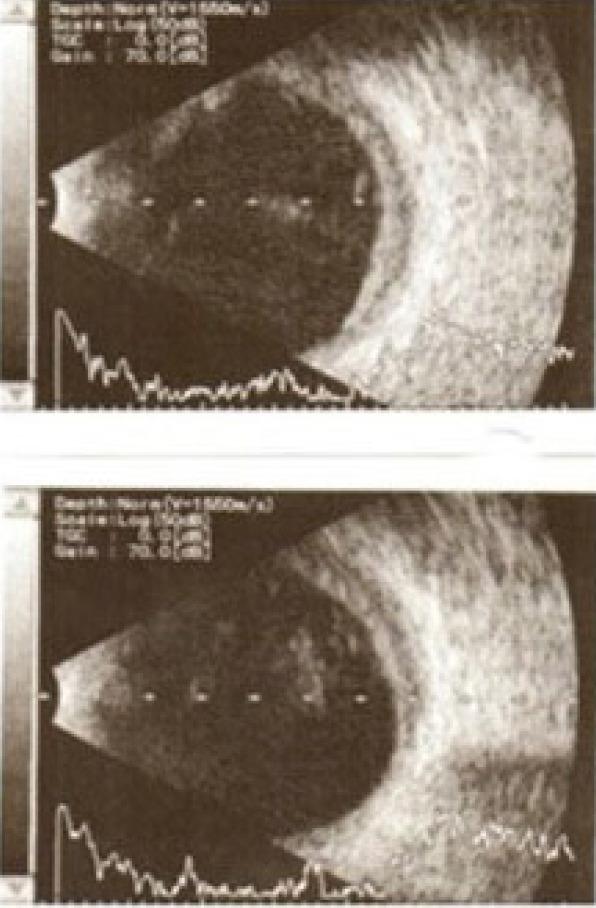

A 61-year-old patient with end-stage liver cirrhosis was admitted for cataract surgery with corrected distance visual acuities (CDVAs) of 0.3, in both eyes. His international correction ratio (INR) for blood coagulation was 2.1 without any anticoagulants, and general anesthesia was contraindicated. He was deemed inoperable for liver transplantation. Two weeks after uneventful phacoemulsification in his right eye under topical anesthesia, he underwent phacoemulsification for the cataract in the left eye. However, during surgery, extensive zonular dialysis was noted and the surgery proceeded with extracapsular cataract extraction and anterior vitrectomy, during which a rapid suprachoroidal hemorrhage (SCH) was noted. The incisions were then rapidly sutured. Intravenous 150 cc of 18% mannitol and 2 mg midazolam and sublingual 5 drops of nifedipine were given, and he was placed in the slightly reverse-trendelenburg position. Following suturation of the incision, the globe was left aphakic, slightly hypertonic with no loss of vitreous through the incisions. The postoperative treatment regimen of topical prednisolone and moxifloxacin eye drops of each per hour, cyclopentolate three times a day, and peroral prednisolone 40 mg was commenced. Despite no retinal reflex on the first day and no light perception for 2 weeks, transscleral SCH evacuation with limited pars plana vitrectomy was performed in the postoperative third week. Despite recurrent hemorrhage and intravitreal inflammatory bands, choroidal detachments regressed slowly with the improvement of CDVA up to 0.6 with aphakic contact lens correction at 3 months. The patient passed away due to complications of liver cirrhosis at 6 months.

一名61岁的终末期肝硬化患者因双眼矫正远视力(CDVA)为0.3而入院接受白内障手术。他在未使用任何抗凝剂的情况下,血液凝固的国际标准化比值(INR)为2.1,全身麻醉被视为禁忌。他被认为无法无法肝移植手术不可行。在右眼局部麻醉下顺利进行超声乳化白内障吸除术两周后,他接受了左眼白内障的超声乳化手术。然而,手术过程中发现广泛的晶状体悬韧带离断,手术改为囊外白内障摘除联合前部玻璃体切除术,在此期间出现了快速的脉络膜上腔出血(SCH)。然后迅速缝合切口。静脉注射150毫升18%的甘露醇和2毫克咪达唑仑,并舌下含服5滴硝苯地平,患者被置于轻度头低脚高位。切口缝合后,眼球呈无晶状体状态,略为高眼压,切口处无玻璃体丢失。开始术后治疗方案,每小时局部使用泼尼松龙和莫西沙星滴眼液,每天三次使用环喷托酯,口服泼尼松龙40毫克。尽管术后第一天无视网膜反射,且两周内无光感,但在术后第三周进行了经巩膜脉络膜上腔出血引流联合有限的睫状体平坦部玻璃体切除术。尽管反复出血和玻璃体内出现炎性条索,但脉络膜脱离随着CDVA的改善而缓慢消退,3个月时无晶状体接触镜矫正后CDVA提高至0.6。患者在6个月时因肝硬化并发症去世。